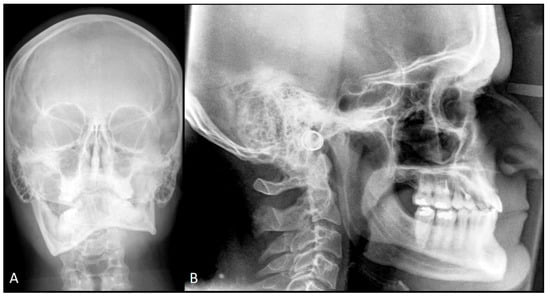

- Decompensating orthodontic treatment

2.1. First Step